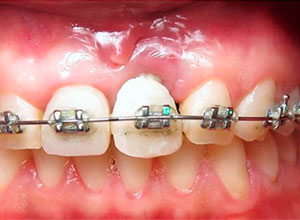

Se realizó distracción alveolar vertical histogénica, incluyendo el implante. La mecánica de la distracción usada en este caso en especial es la tracción elástica y/o alámbrica mediante brackets de ortodoncia.

Se empezó a hacer la distracción, primero con un arco recto y posteriormente con elásticos haciendo el recorte con el borde incisal conforme se va bajando el implante con el bloque óseo.